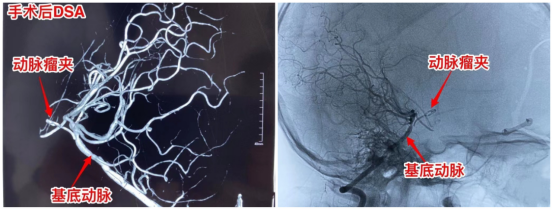

术中,周忠清主任小心翼翼地用骨膜片围绕动脉瘤颈部,动脉瘤夹夹闭动脉瘤颈部,导致动脉瘤颈部断裂、脱落,用骨膜片包裹基底动脉,动脉瘤颈表面垫肌肉片,再用动脉瘤夹夹紧骨膜片,封闭基底动脉破口,达到加固基底动脉的效果,最后顺利切除动脉瘤。手术持续6小时,顺利完成,成功将聪聪脑子的“两个炸弹”同时拆掉。

术后行脑血管造影,显示基底动脉血流通畅,顺利度过恢复期,聪聪安全出院,出院前没有明显的神经功能障碍,行动自如,聪聪父母悬着的心终于落地。